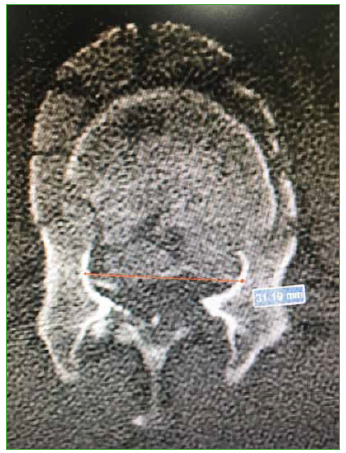

- Distancia interpedicular (distancia más amplia medida en milímetros entre ambos pedículos de la vértebra fracturada en el corte axial de TC) (Figura 1).

Figura 1.

Tomografía computarizada, corte axial. Distancia interpedicular.